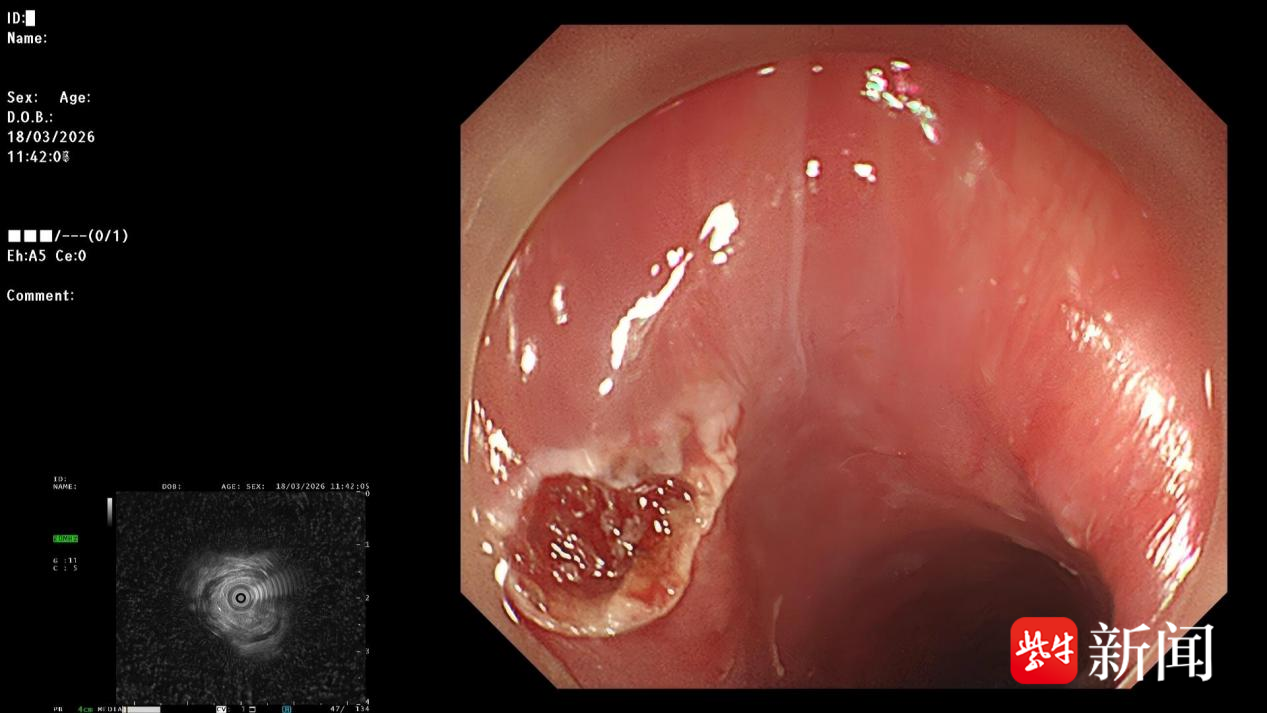

超声内镜查找异物

在超声内镜的精准引导下,手术团队运用ESD专用切开刀,精细切开患者食管的粘膜及粘膜下层,逐层剥离组织,安全暴露嵌顿于肌肉中的鱼刺,用活检钳稳稳夹住并将其完整取出,随后对手术创面进行了妥善止血。整个手术过程微创、精准,无明显并发症。

食管ESD手术取异物